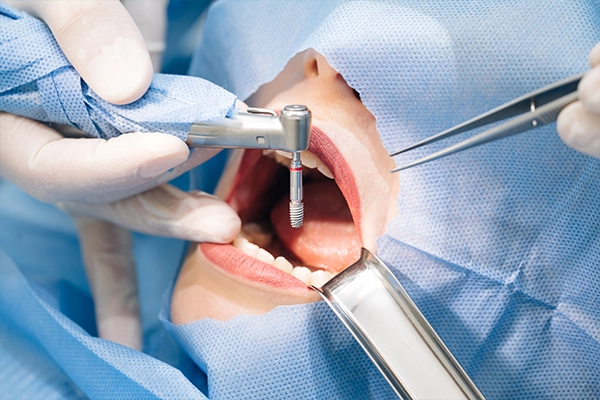

インプラント埋入

左上1番は抜歯後、抜歯即時は非適応なためリッジプリザベーション(※1)を行い待時埋入を行いました。

リッジプリザベーション後、骨が十分に成熟したため待時埋入を行いました。

埋入時の様子